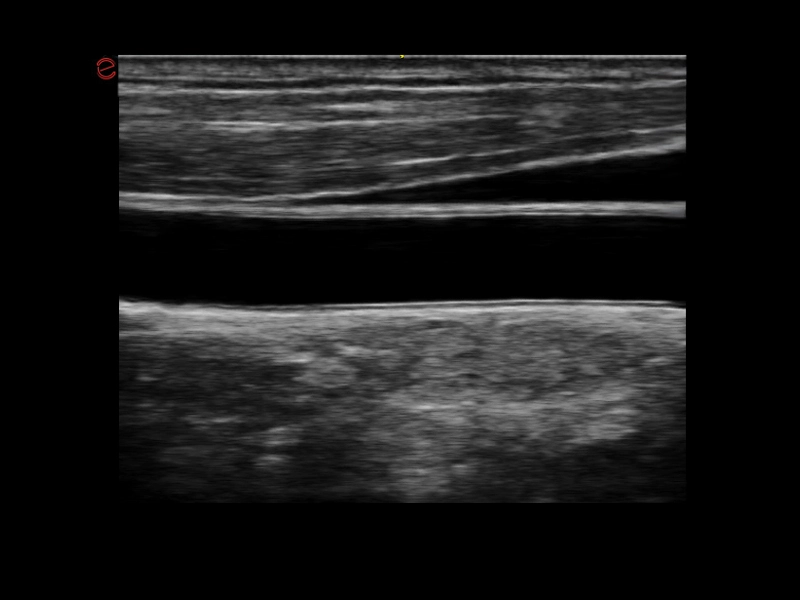

MyLab™X1 Go - Cardiovascular IMT

MyLab™X1 Go - Cardiovascular IMT